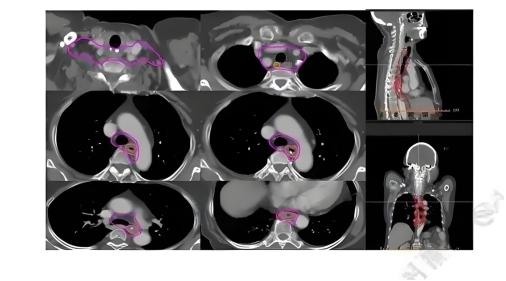

• 阶段1:定位与计划(13天)

• 定位期:定制身体固定模具,通过CT/PET影像勾画肿瘤靶区。

• 计划期:医生计算剂量方案,确保射线聚焦肿瘤,避开健康组织。